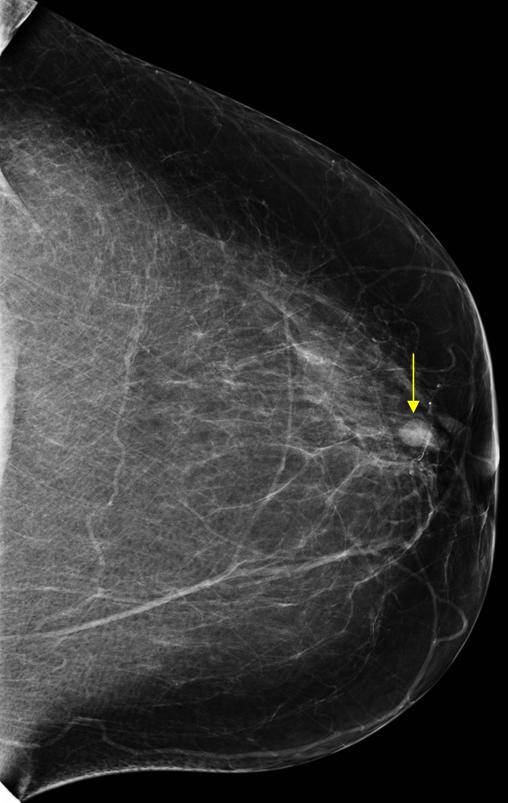

Ung thư vú

» Thông tin: Nữ giới – 69 tuổi.

» Lâm sàng: Kiểm tra sức khỏe.